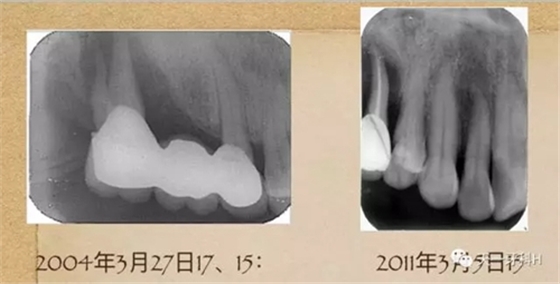

2004年3月27日17:

17牙槽骨已經(jīng)破壞到了根尖,這樣的牙齒的松動(dòng)度已經(jīng)到達(dá)了三度,17的每一次搖動(dòng)都會(huì)造成固定橋另一端的基牙15的搖動(dòng),久而久之15的牙槽骨也被破壞了,此時(shí)應(yīng)該盡早拆除固定橋。

2011年3月3日拍攝:

2011年3月3日,這個(gè)患者又來(lái)到了診所,此時(shí)的她上頜的烤瓷橋已經(jīng)沒(méi)有了,做基牙的牙齒右上七和右上五沒(méi)有了,右上四遠(yuǎn)中的牙槽骨也已經(jīng)破壞到根尖四分之一了,左上八沒(méi)有了,只剩下左上五,下頜烤瓷橋雖然還在,但左下八近中的牙槽骨吸收也到達(dá)根尖了。

15 的牙槽骨破壞已經(jīng)到達(dá)根尖,這樣的牙齒就是無(wú)法保留的牙齒,只能拔掉。回頭看2004年的15,盡管有牙周膜間隙的改變,如果當(dāng)時(shí)患者聽(tīng)從勸導(dǎo),拆除烤瓷橋保住15號(hào)牙是毫無(wú)懸念的。我不知道這個(gè)病例的發(fā)生、發(fā)展過(guò)程

能否讓你們醒悟,牙周病患者做烤瓷牙要慎之又慎!